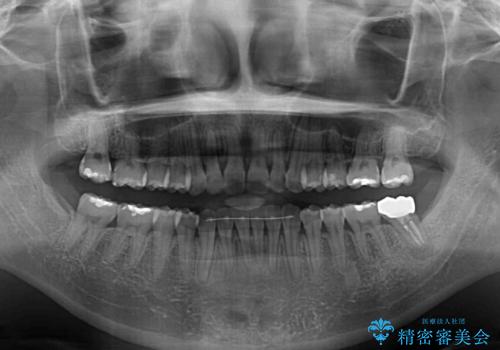

長時間のマウスピース装着に協力いただき、自然な口元に仕上げることができました。

気になっていた銀歯もオールセラミッククラウンで本物の歯のようになり、患者様には大変満足していただきました。